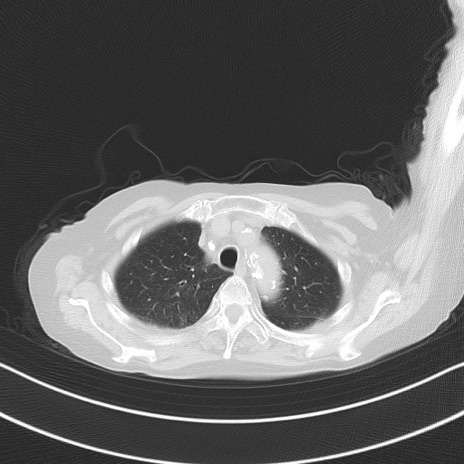

横断像